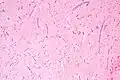

Micrograph of an atrial myxoma. H&E stain.